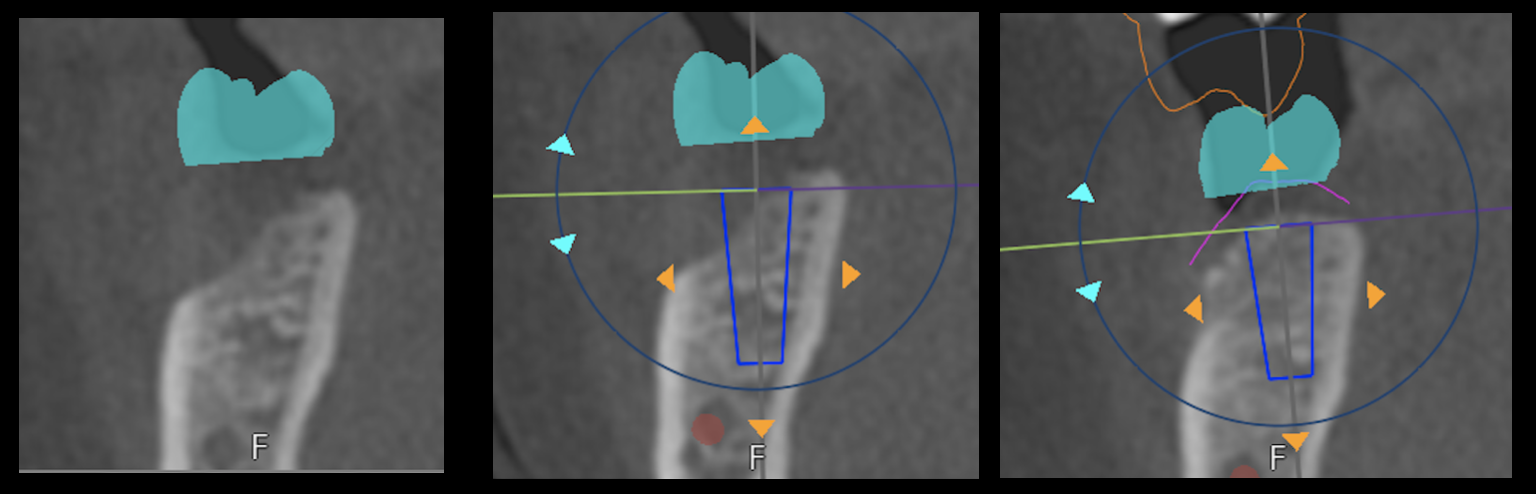

A tooth was extracted and no graft was placed. The left and center pictures are pre-graft. A CT scan was imported into treatment planning software with a virtual implant placed in ideal position. This shows a lack of bone to support the implant. A b…

A tooth was extracted and no graft was placed. The left and center pictures are pre-graft. A CT scan was imported into treatment planning software with a virtual implant placed in ideal position. This shows a lack of bone to support the implant. A bone graft was placed to augment the ridge. Far right picture is of a CT scan shows adequate bony support for an implant. This is a great example of two things: 1. How bone loss occurs after a tooth extraction and 2. how a bone graft can rebuild a resorbed ridge to allow placement of an implant.